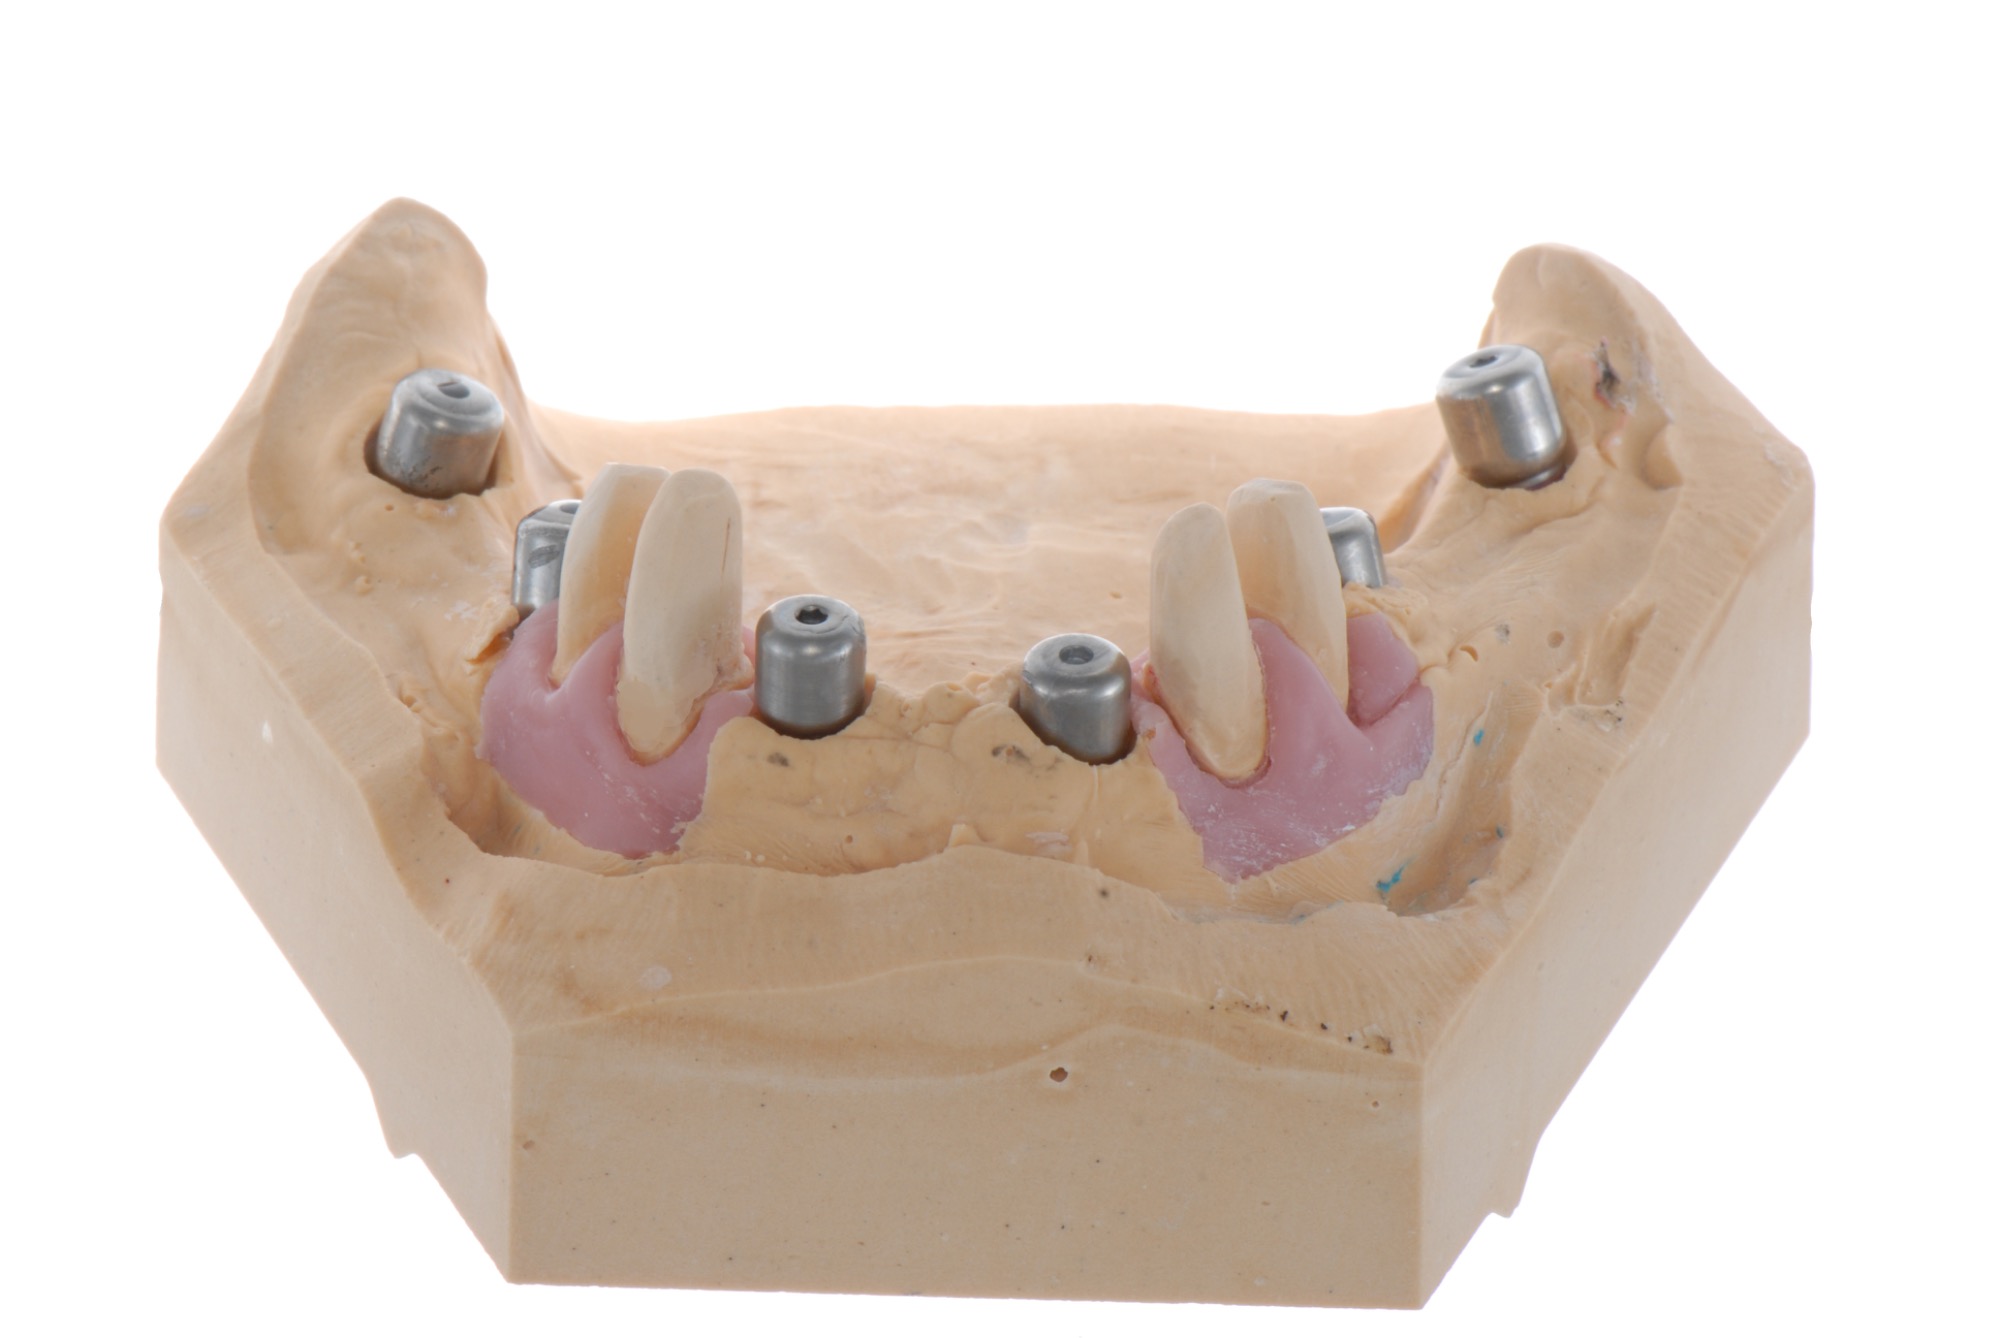

Verschraubte Implantatbrücken fühlen sich für den Patienten an wie die eigenen Zähne.

Implantsteg verankerte Brücke. Für den Patienten abnehmbar, aber der Tragekomfort von festen Zähnen.

Implantatbrücke zur Wiederherstellung der Zahn- und Zahnfleischanteile mit verschraubten Brücken.